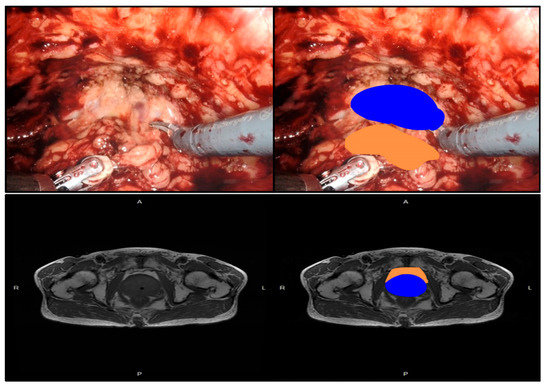

- Zhang, Q.; Sun, L.J.; Qi, J.; Yang, Z.G.; Huang, T.; Huo, R.C. Periprostatic adiposity measured on magnetic resonance imaging correlates with prostate cancer aggressiveness. Urol. J. 2014, 11, 1793–1799. [Google Scholar]

- Woo, S.; Cho, J.Y.; Kim, S.Y.; Kim, S.H. Periprostatic fat thickness on MRI: Correlation with Gleason score in prostate cancer. AJR Am. J. Roentgenol. 2015, 204, W43–W47. [Google Scholar] [CrossRef]

- Dahran, N.; Szewczyk-Bieda, M.; Wei, C.; Vinnicombe, S.; Nabi, G. Normalized periprostatic fat MRI measurements can predict prostate cancer aggressiveness in men undergoing radical prostatectomy for clinically localised disease. Sci. Rep. 2017, 7, 4630. [Google Scholar]